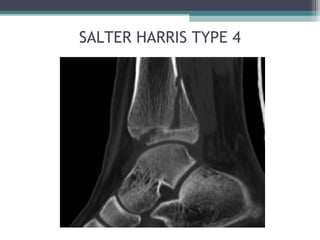

• SALTER-HARRIS (1963) – MOST WIDELY USED:

▫ TYPE 4: FRACTURE RUNS LONGITUDINALLY SPLITTING

EPIPHYSIS, PHYSIS & METAPHYSIS

SALTER HARRIS TYPE 4